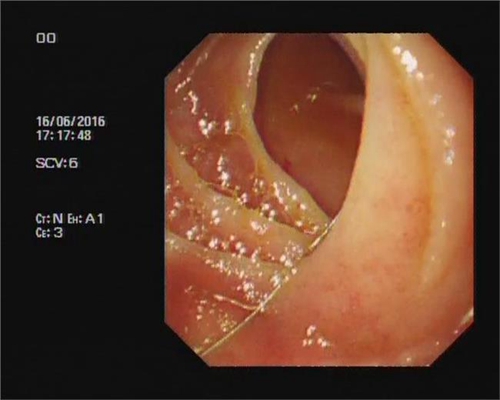

食道炎圖片